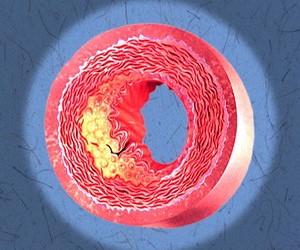

Dislipidemia reprezint? o tulburare a metabolismului lipidic caracterizat? prin acumularea de gr?simi ce favorizeaz? apari?ia ateromatozei, physician there steatozei hepatice, pancreatitei ?i altor complica?ii metabolice.

Statinele sunt inhibitori ai enzimei HMG-CoA reductază, care intervine în sinteza colesterolului. Prin blocarea acestei enzime, statinele scad sinteza de colesterol și nivelul plasmatic de LDL-C (colesterolul “rău”, care favorizează ateromatoza). Pe lângă efectul hipocolesterolemiant, statinele scad și sinteza de VLDL și consecutiv trigliceridemia și cresc modest nivelul HDL-C (colesterolul “bun”). Ca efecte adverse, statinele pot da mialgii, miopatie (caz în care trebuie dozată enzima musculară creatin-kinază), rabdomioliză, citoliză hepatică (cu creșteri ale transaminazelor la circa 10% din pacienți). În ciuda potențialului hepatotoxic, statinele pot fi administrate în siguranță la pacienții cu transaminaze ușor-moderat crescute, acestea fiind cel mai probabil atribuibile unei steatoze hepatice non-alcoolice, fiind vorba despre pacienți dislipidemici; în fapt, prin ameliorarea profilului lipidic statinele nu numai că reduc riscul cardiometabolic dar ameliorează și nivelul transaminazelor. Ca interacțiuni medicamentoase, gemfibrozil crește riscul de rabdomioliză iar inhibitorii enzimatici ai CYP450 amplifică toxicitatea statinelor. Statinele sunt recomandate pentru în hipercolesterolemie (asociată sau nu cu hipertrigliceridemie), steatoză hepatică, după accident vascular cerebral, la pacienții arteriopați (coronaropatie, ateromatoză carotidiană, arteriopatie periferice) și la cei cu risc cardiovascular înalt. Exemple de statine sunt: atorvastatină (Sortis), simvastatină (Simvacard, Simvor, Vasilip, Zeplan, Zocor), fluvastatină (Lescol), rosuvastatină (Crestor), lovastatină (Medostatin), pravastatină (Pralip, Pravator). Administrarea se face seara deoarece mare parte din colesterol se sintetizează pe durata nopții. Statinele sunt contraindicate în sarcină.

Fibrații sunt hipolipemiante care cresc activitatealipoprotein-lipazei, ducând la scăderea VLDL și IDL, scăderea modestă a LDL, creșterea HDL și scăderea trigliceridelor. Principala indicație este în hipertrigliceridemie. Principalii reprezentanți ai clasei sunt fenofibrat (Lipanthyl, Lipofib), benzafibrat (Regadrin), ciprofibrat (Lipanor), clofibrat și gemfibrozil. Ca reacţii adverse pot apărea: miozită, tulburări dispeptice, creşterea transminazelor, scăderea libidoului, litiază biliară. Fibrații sunt contraindicați în sarcină, insuficienţă hepatică sau renală.